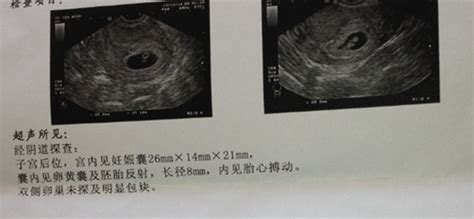

怀孕8个月胎儿b超图

怀孕8个月胎儿彩超图